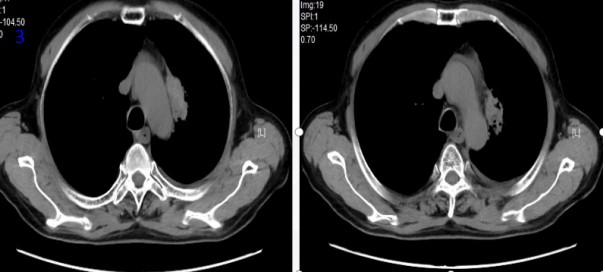

2023年12月26日再程放療后24個月復(fù)查胸部CT可見腫瘤明顯縮?。▓D9),RECIST評價PR。2024年2月18日、2024年12月22日、2025年4月15日在外院行胸部CT提示“左肺上葉及縱隔旁見斑片條索陰影,考慮增值性病灶”。2025年8月20日電話隨訪,患者正常生活,未訴任何不適?;颊咴俪谭暖熀?年8個月,病情穩(wěn)定,總生存超過5年,達(dá)到臨床治愈效果。

圖9 再程放療后24個月胸部CT